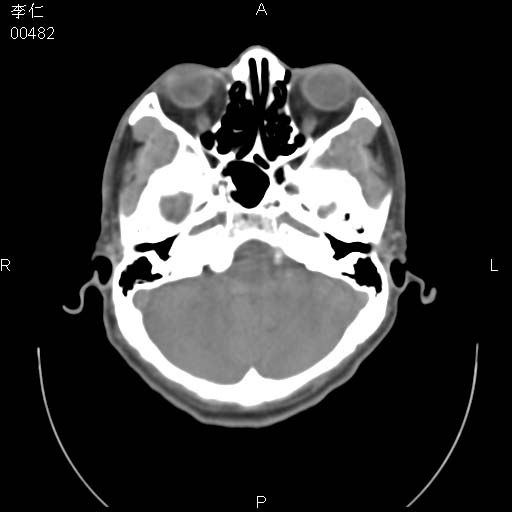

患者男,45岁。于二月前发现左眼稍肿,去看眼科,查肾功(—),来查ct,我看到的是左侧上眼睑内低密度影,ct值是-600到-700hu。

副鼻窦发育畸形所致。

是气体 前组筛窦发育过度所致,如果有外伤就不排除骨折

是一个副鼻窦的正常变异,脂肪瘤的密度不可能这么低,-600到-700.

正常的,结膜间的气体,再不然就薄层扫描重建一下

左侧眼球壁光滑,未见异常密度灶,眶内结构清晰,眼内肌、视神经均正常。所见低密度灶,本人考虑:1、五官科翻上睑造成;2、炎症(产气细菌感染)。